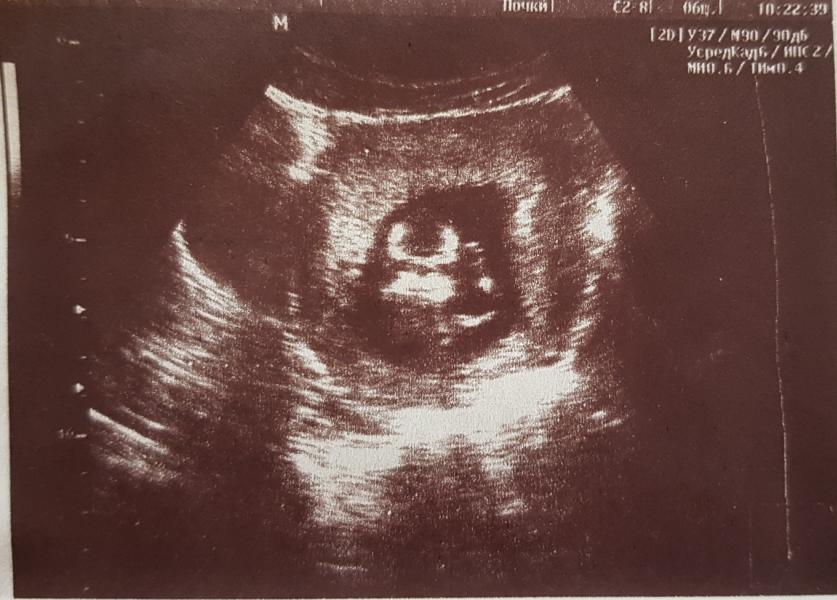

В общем, сходила я на узи в Кольпос к Муратовой.

Могу сказать, мне она понравилась, всё посмотрела, пальчики-косточки посчитала, всё измерила, показала нам нашего маленького человечка🥰 Сделала вот такой чудесный портрет улыбашки🥰 Пол пока не знаем, в следующий раз уже посмотрим❤